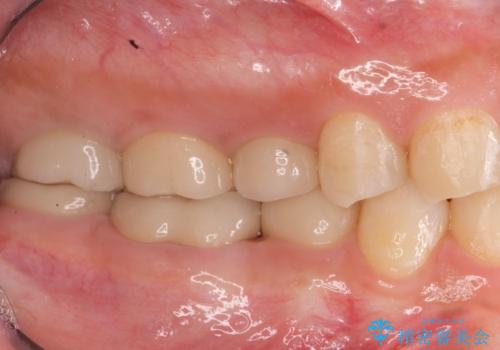

奥歯は既に根管治療が為されクラウンを装着する必要性がある状態ですが、歯の高さが低くクラウンの安定性・強度を担保するために歯周外科を行う治療計画としました。

歯周外科を行うことで、歯ぐきの位置を下げ歯の高さを作り出し安定したクラウンの装着が可能となります。また同時に舌の邪魔となっていた骨隆起の除去を行うこととしました。

- 37.4万円(ジルコニアクラウン×2・仮歯×2・歯周外科手術)費用は治療当時の料金となります